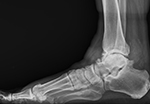

Our standing xray protocol is used to determine the overall shape, structure and integrity of the ankle and foot, while facilitating a comparison with the opposite side. The x-rays also assist in the evaluation of associated conditions.